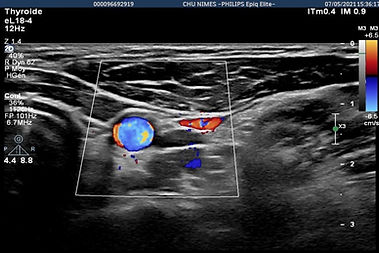

paciente de 40 añoshipertiroidismo biológico (TSH 0,08)

nódulo caliente en gammagrafía

nódulo ístmico derecho de 4,91 cc muy vascularizado